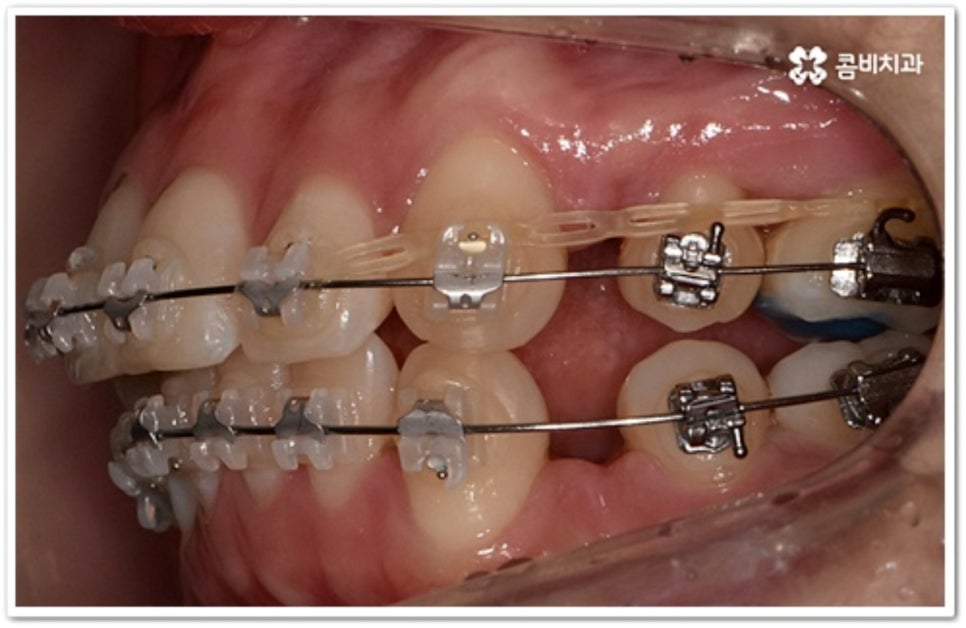

그러나 만약 덧니가 많고 부정 교합 정도가 심하거나 치아가 고르게 배열될 공간이 크게 부족하다면 덧니 발치 교정 치료를 진행하게 되는데, 이때 보통 치아 중에 기능이 가장 적은 소구치를 우선적으로 발치하게 되지만 (사진에서 확인할 수 있는 케이스) 환자분들의 상황에 따라 필요 없는 사랑니를 발치하고 어금니부터 뒤로 밀어 자리를 잡아주거나 충치 또는 짧아진 치근 등으로 심하게 손상된 치아가 있는 소구치를 우선적으로 발치하여 교정 치료를 진행하기도 하고, 필요시 임플란트와 병행하여 치료를 진행하는 경우도 있습니다. 따라서 먼저 자신의 상황에 대해서 면밀하게 검진을 받아보고 자세한 치료 계획에 대해서 의료진과 충분하게 상담해 보시는 게 좋을 거예요.

송곳니는 끝이 뾰족하여 질긴 음식을 잘게 찢는 데 용이하며 씹을 때 아래턱의 움직임을 조절해 주는 등 저작 기능을 원활하게 수행하는데 큰 도움을 주고 있습니다. 또한 뿌리가 길고 크기가 커서 주변 치아 지지 및 치열과 안모의 형태를 잡아주는데 중요한 역할을 하기 때문에 뽑지 않고 위치만 제자리로 이동시켜 상하악 균형을 맞추면서 턱관절을 관리하는 방식으로 덧니 발치 교정 치료를 진행하고 있는데요. 이때 입 모양이나 턱의 각도, 안모의 조화를 전체적으로 고려하지 않고 무리하게 덧니 발치 교정을 하게 되면 합죽이나 옥니와 같은 부작용을 낳을 수 있으니 주의할 필요가 있어요.

치아는 제자리로 돌아가려는 성질을 가지고 있어서 덧니 발치 교정이 끝난 후 일정 기간 동안은 유지 장치를 착용하여 이를 예방하고 정기 검진을 꼬박꼬박 받으면서 사후 관리를 철저하게 해 주는 게 좋을 거예요. 유지장치에는 고정식과 가철식이 있는데 치아 안쪽에 얇은 철사를 붙이는 고정식 (사진에서 볼 수 있는 사례) 은 앞니가 틀어지는 것을 방지해 주고, 뺐다 꼈다 하는 가철식은 교정 치료할 때 악궁 확장을 한 경우 전체 치열을 유지하기 위해 필요한 방식이라고 할 수 있어요. 환자분들 각각의 치료 과정이나 구강 상태에 따라 둘 중 하나를 선택하거나 두 가지 다 해야 하는 경우가 생길 수 있습니다.